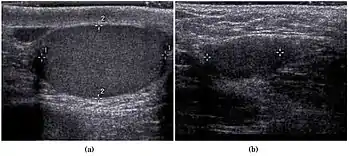

Scrotal ultrasonography of undescended testis: (a) Normal testis in the scrotum (b) Atrophic and decreased echogenicity of the contralateral testis of the same patient seen in the inguinal region

In the minority of cases with bilaterally nonpalpable testes, further testing to locate the testes, assess their function, and exclude additional problems is often useful. Scrotal ultrasound or magnetic resonance imaging performed and interpreted by a radiologist can often locate the testes while confirming absence of a uterus. At ultrasound, the undescended testis usually appears small, less echogenic than the contralateral normal testis and usually located in the inguinal region. With color Doppler ultrasonography, the vascularity of the undescended testis is poor.